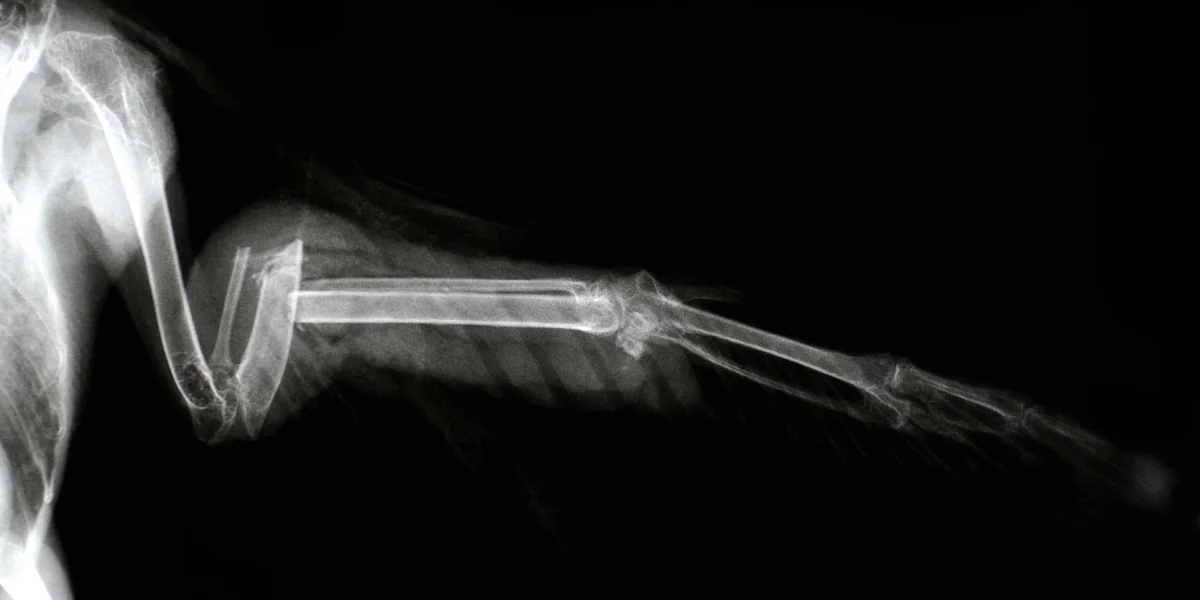

Vögeln den gebrochenen Flügel verarzten? So romantisch ist es meist nicht Foto: Scott Camazine/Alamy

Einen Vogel mit gebrochenem Flügel verarzten, bei der Geburt von Kälbchen helfen und täglich zig Hunde und Katzen streicheln – so vielleicht stellen sich Kinder den Alltag von Tierärzt*innen vor. Auch unter Erwachsenen ist die Annahme verbreitet, Veterinär*innen führten ein erfülltes, glückliches Berufsleben, schließlich verbringen sie den ganzen Tag mit Tieren und tun nebenbei noch etwas Gutes. Die Realität aber ist: In keinem Beruf ist das Suizidrisiko so hoch wie in diesem.